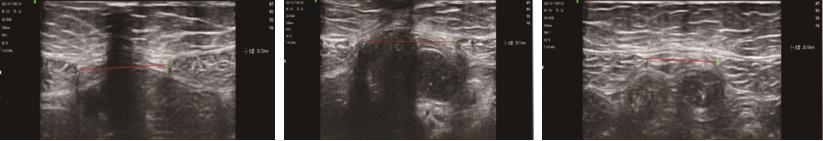

• 高频超声用于评估Flexi-bar运动训练联合脉管电刺激治疗后产后腹直肌分离变化的临床价值

摘要:目的 探讨高频超声用于评估Flexi-bar运动训练联合脉管电刺激治疗后产后腹直肌分离变化的临床价值。方法 回顾性分析常州市妇幼保健院2022年5月—2024年4月收治的87例产后腹直肌分离患者的病历资料。根据治疗方法不同将患者分成观察组(45例)与对照组(42例),观察组采用Flexi-bar运动训练联合脉管电刺激治疗,对照组采用脉管电刺激治疗。采用高频超声评估患者腹直肌间距离,对比两组的腹围、腹直肌间距离、腹直肌均方根、肌纤维力及生活质量。结果 观察组治疗前后下腹围、中腹围和上腹围的差值均大于对照组(P <0.05)。观察组治疗前后屈曲状态下脐下3 cm、脐上3 cm和脐中腹直肌间距离的差值均大于对照组(P <0.05)。观察组治疗前后静息状态下脐下3 cm、脐上3 cm和脐中腹直肌间距离的差值均大于对照组(P <0.05)。观察组治疗前后腹直肌最大自主等长收缩振幅均方根、盆底Ⅱ类肌纤维肌力平均值、盆底Ⅰ类肌纤维肌力最大值的差值均大于对照组(P <0.05)。观察组治疗前后生活质量评分的差值大于对照组(P <0.05)。结论 Flexi-bar运动训练联合脉管电刺激可改善产后腹直肌分离患者生活质量与盆底肌纤维肌力,缩小患者腹围,促进产后腹直肌分离的恢复,且高频超声可有效评估患者恢复情况与腹直肌分离情况。